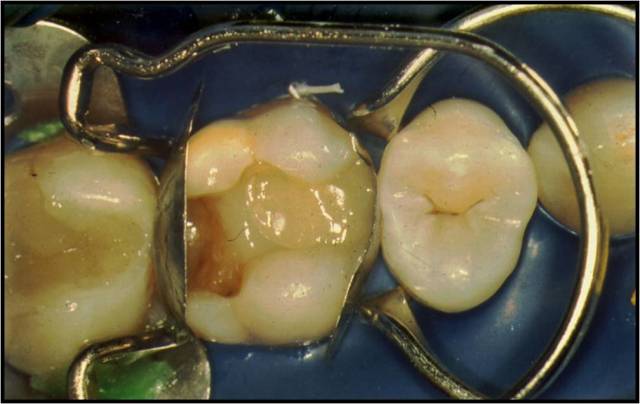

——成型片技术(触点恢复)

成型片技术的目的:

是使修复体有理想成型

有效恢复接触区

是防止悬突产生的关键技术

前后牙的修复都涉及恢复触点的问题

通常情况下,前牙触点恢复主要使用塑料成型膜,通过技术技巧来完成

而后牙二类洞则需要更多的辅助工具来完成的触点恢复,如QUICK RING 、Palodent、Danvill Ring等都是完整的触点恢复辅助技术系统,包括钢环、楔子(木制、塑料制)、成型片等。

此外,常用的成型夹还有环状TOFFLEMIRE,器械有Optra-matrix,Optra-contact,CCI等。这些工具都有各自的操作技术要领,需结合具体情况进行选择使用。

熟练把握成型片技术,可以有效提高树脂修复的效率。